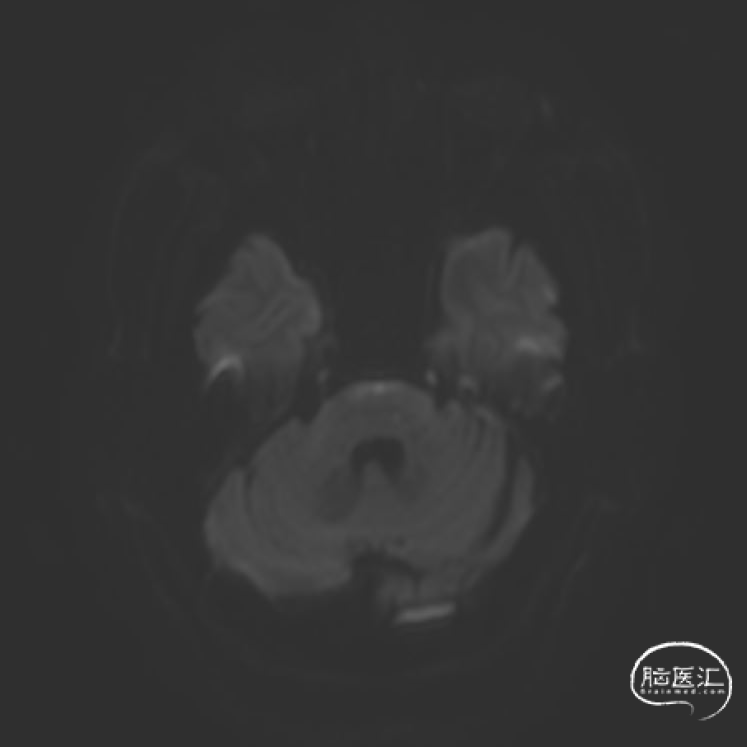

➢2023年10月28日

头颅MRI平扫:脑桥急性脑梗死,基底动脉近端重度狭窄。

➢2023年10月31日

头颅MRI平扫:脑桥、左侧小脑半球、颞叶多发急性/亚急性脑梗死。

➢2023年11月06日

头颅MRI平扫:脑桥、左侧中脑、左侧桥臂急性脑梗死。

➢2023年11月13日

头颈部CTA:头颈部动脉粥样硬化,右侧椎动脉颅内段及两侧大脑后动脉重度狭窄,基底动脉闭塞。

➢2023年11月14日

头颅MRI平扫+HRMRI:脑桥、中脑急性/亚急性脑梗死;双侧桥臂变性。

HRMRI:基底动脉闭塞并斑块合并局部出血;左侧大脑后动脉P1段斑块形成,相应管腔闭塞,左侧椎动脉V2-V4段斑块形成,相应管腔中重度狭窄,左侧椎动脉V4段管壁弥漫性增厚,相应管腔中度狭窄;右侧大脑后动脉纤细。